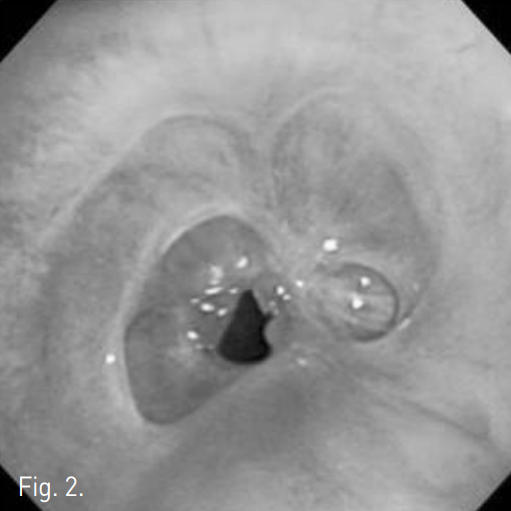

Fig. 3

A-C. Successful luminal dilatation was done using 15mm and 20mm balloon catheters.